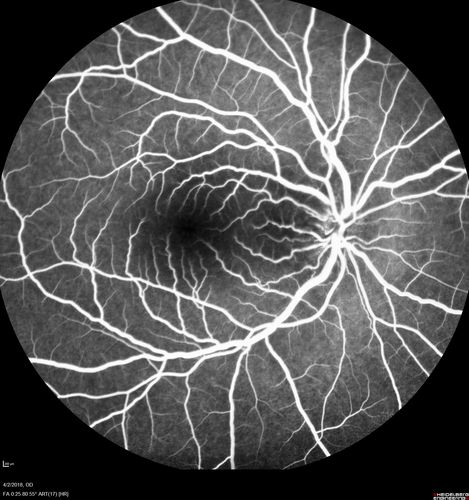

Cat Scratch - Neuroretinitis OD AND retinitis OS - Bartonella henselae positive

27 year old female with exposure to cats and prior fever.  Reports with recent vision loss right eye.  She was treated with doxycycline and within 2 weeks the right eye looks better.  Then she skipped all follow-up visits.  The right eye presented 20/200 and the left 20/16